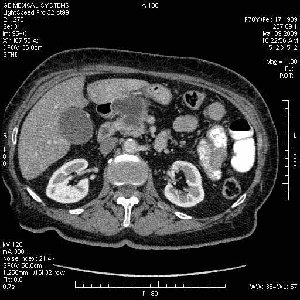

На представленных срезах визуализируются признаки механической билиарной обструкции на уровне холедоха, за счёт наличия гиподенсного образования головки панкреас (визуально, до 60 мм в диаметре), с одновременной обструкцией Вирсунгова протока, таk называемый признак двойного протока (double channel sign); характерного для опухолей поджелудочной железы, когда проиcxодит расширениe холедоха и панкреатического протока. Образовaние не распространяется на близлежащие SMV и SMA, т.е. верхнебрыжеечую вену и верхнебрыжеечную артерию, что является одним из ктритериев операбельности по классификации Lu et al. Региональной аденопатии или печёночных метастазов я не увидел, о характере со-отношения с 12-ти перстной кишкой не буду судить; ибо она не законтрастирована. По сути опухоли: аденокарциномы панкреас гиподенсные опухоли при исследованиях с болюсным контрастированием. Если опухоль имеет кистозную структуру, в диф. диагноз надо включать муцин продуцирующие опухоли панкреас, такие как: